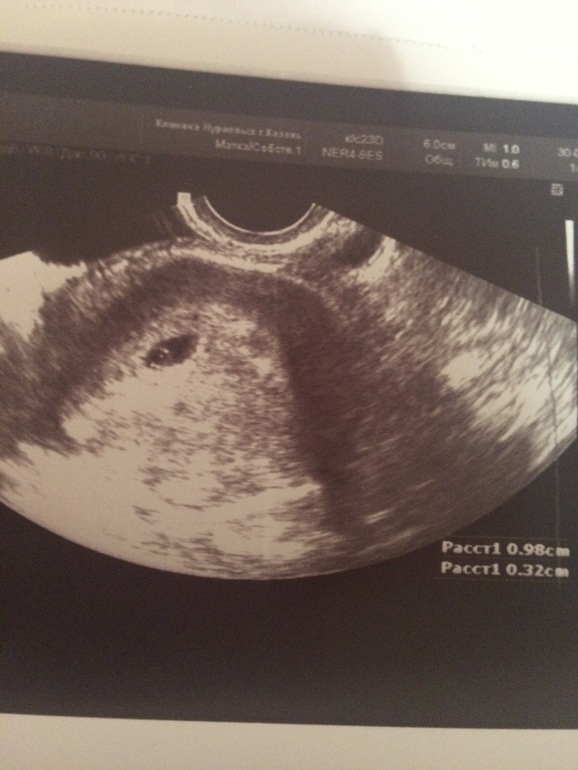

Ну 8 мм это приличный размер, а фото нет у Вас? У меня было 10 мм

Мне отдельно показывали матку с ПЯ и отдельно желтые тела в яичнике

По своему фото я тоже ничего не понимаю...

А трапециевидное затемнённые контуры вокруг это матка. У меня всегда смотрят отдельно матку, отдельно яичники. Пусть вам также посмотрят

Я так понимаю, на вашем фото ПЯ и в нем ЖМ?Если это так, то почему в моем нет?

Да ПЯ 10 мм и ЖМ 3 мм. Сходите через пару дней снова на УЗИ, и пусть вам прям четко ПЯ в матке покажут. Я думаю все у вас будет хорошо